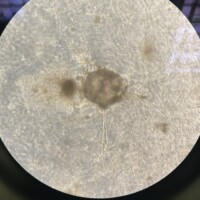

¿Qué tipos de muestras se almacenan?

En el Biobanco se almacenan muestras sanguíneas, orina, pelo, uñas, líquido cefalorraquídeo, médula, células a viabilidad para cultivo, DNA/RNA, tejidos tumorales o sanos excedentes de cirugías y muchas más cosas.